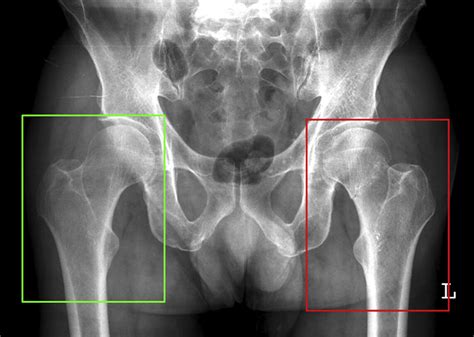

Diagnosing a hip stress fracture can be challenging because early stress fractures often do not show up on standard X-rays. A physician will typically start with a physical examination, checking for tenderness in the groin and evaluating how pain is triggered by specific movements.

• X-rays: While often negative in the first few weeks, they are still used as an initial screening tool.

If the fracture occurs on the tension side (the top) of the femoral neck, it is considered high-risk, and surgery is almost always required to fix the bone and prevent a complete break. Surgery typically involves internal fixation using screws or pins to stabilize the area.